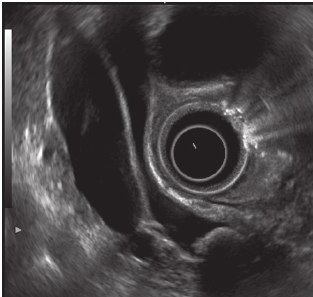

✅Эндосонография (синоним эндо-УЗИ, ЭУС)

метод, сочетающий в себе возможности одновременной эндоскопической и ультразвуковой диагностики заболеваний ЖКТ, поджелудочной железы, желчных протоков и печени. Данный метод позволяет хорошо визуализировать все отделы поджелудочной железы, ее главный проток, общий желчный проток - от терминального отдела до бифуркации (что достаточно плохо визуализируется при МРХПГ), большой дуоденальный сосочек. Разрешающая способность современных эхоэндоскопов позволяет обнаружить изменения от 2 мм.

Также есть возможность использования в клинической практике внутрипротоковой эндосонографии. В этом случае ультразвуковой датчик заводится в холедох с помощью дуоденоскопа во время выполнения ЭРХПГ. Метод дает возможность провести сканирование стенки протока и окружающих его тканей. Данное исследование позволяет определить генез стриктуры, ее протяженность, глубину инвазии.

Тонкоигольная аспирационная биопсия под ЭУС контролем проводится для морфологической оценки причины билиарной гипертензии. Метод позволяет выполнить забор цитологического содержимого из образований от 5 мм.